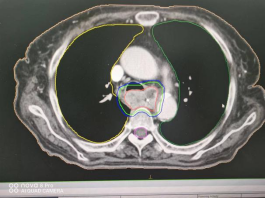

1、肺癌横断面及矢状面肿瘤处治疗剂量显示图

2、咽部肿瘤横断面及矢状面治疗剂量显示图

3、计划系统效果图:黄色线内-蓝色线外深颜色区域为高剂量区域,黄色线外及蓝色线内为低剂量区域。即照射剂量区域可按肿瘤治疗的需要进行调节。